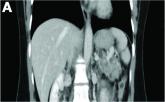

Clinical Challenges - July 2019